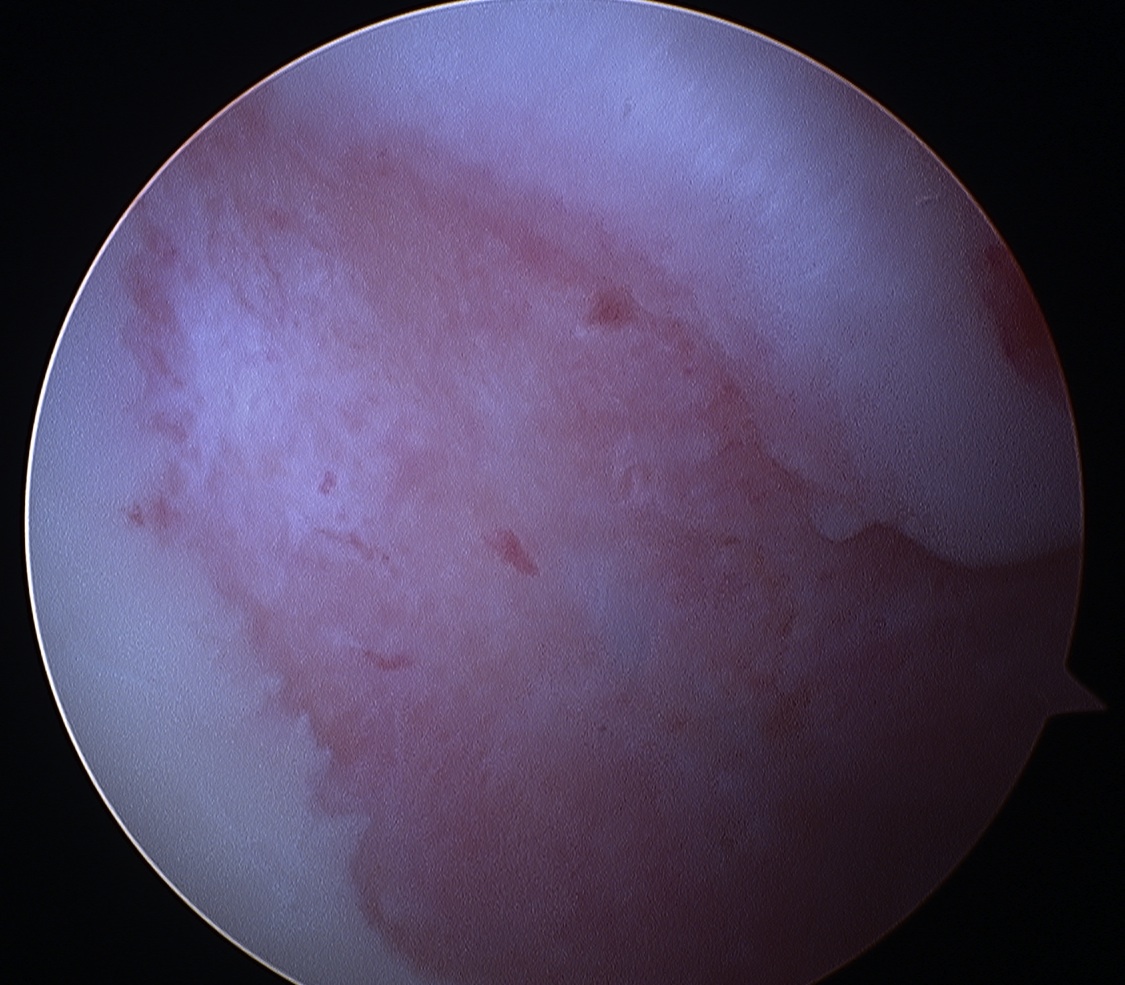

Glenohumeral joint assessment

Labrum

Anterior inferior labral tears |

SLAP tears | Posterior labral tears |

|---|---|---|

|

Below equator 3 - 6 o'clock |

||

|

|

|